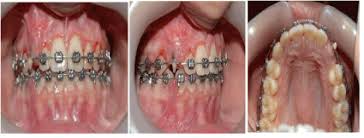

This facilitates eruption and orthodontic traction. The difference in time required for the two techniques was statically significant (p = 0.000). 5.3.1 open exposure 5.3.2 closed eruption technique 5.3.3 open versus closed eruption techniques. Patients perception of recovery after exposure of impacted teeth: If a canine is associated with severe resorption of the root of the incisor, an open exposure is not indicated since it endangers the vitality and existence of the incisor. If the crown is positioned mesial to the lateral incisor, a closed technique for the pataltal eruption of canine. Two techniques for exposing palatal canines are routinely used in the uk: The mean surgical time table 3 for open eruption technique was 22.31 ± 1.98 min as compared to 30.87 ± 2.38 min to closed eruption technique.

Chaushu s(1), becker a, zeltser r, vasker n, chaushu g. Preorthodontic exposure and autonomous eruption The open exposure technique consists of surgical removal of the tissue covering the tooth, leaving it exposed to the oral cavity. Given the reported success of forced eruption, the technique requires… continue reading The present study provides information to patients and clinicians. Duration of surgical procedure (in min) click here to view Dr vanarsdall recommends open exposure with a repositioned gingival flap (pediculated connective tissue graft) above the impacted canine. Apically position flap the goal is to choose a technique that exposes the canine within the a zone of keratinized mucosa without involvement of the cementoenamel junction 27. The open eruption technique may be performed in two different ways, as described below. If the canine crown is positioned distal to the mesial aspect of the lateral incisor, an open technique is performed. Forced eruption can preserve the natural root system and related periodontal architecture, resulting in years of additional service for the patient. Open eruption through a window; In this technique sufficient space.

If the canine crown is positioned distal to the mesial aspect of the lateral incisor, an open technique is performed open'er. (1) window technique, (2) full flap open procedure, and (3) apically repositioned flap technique.